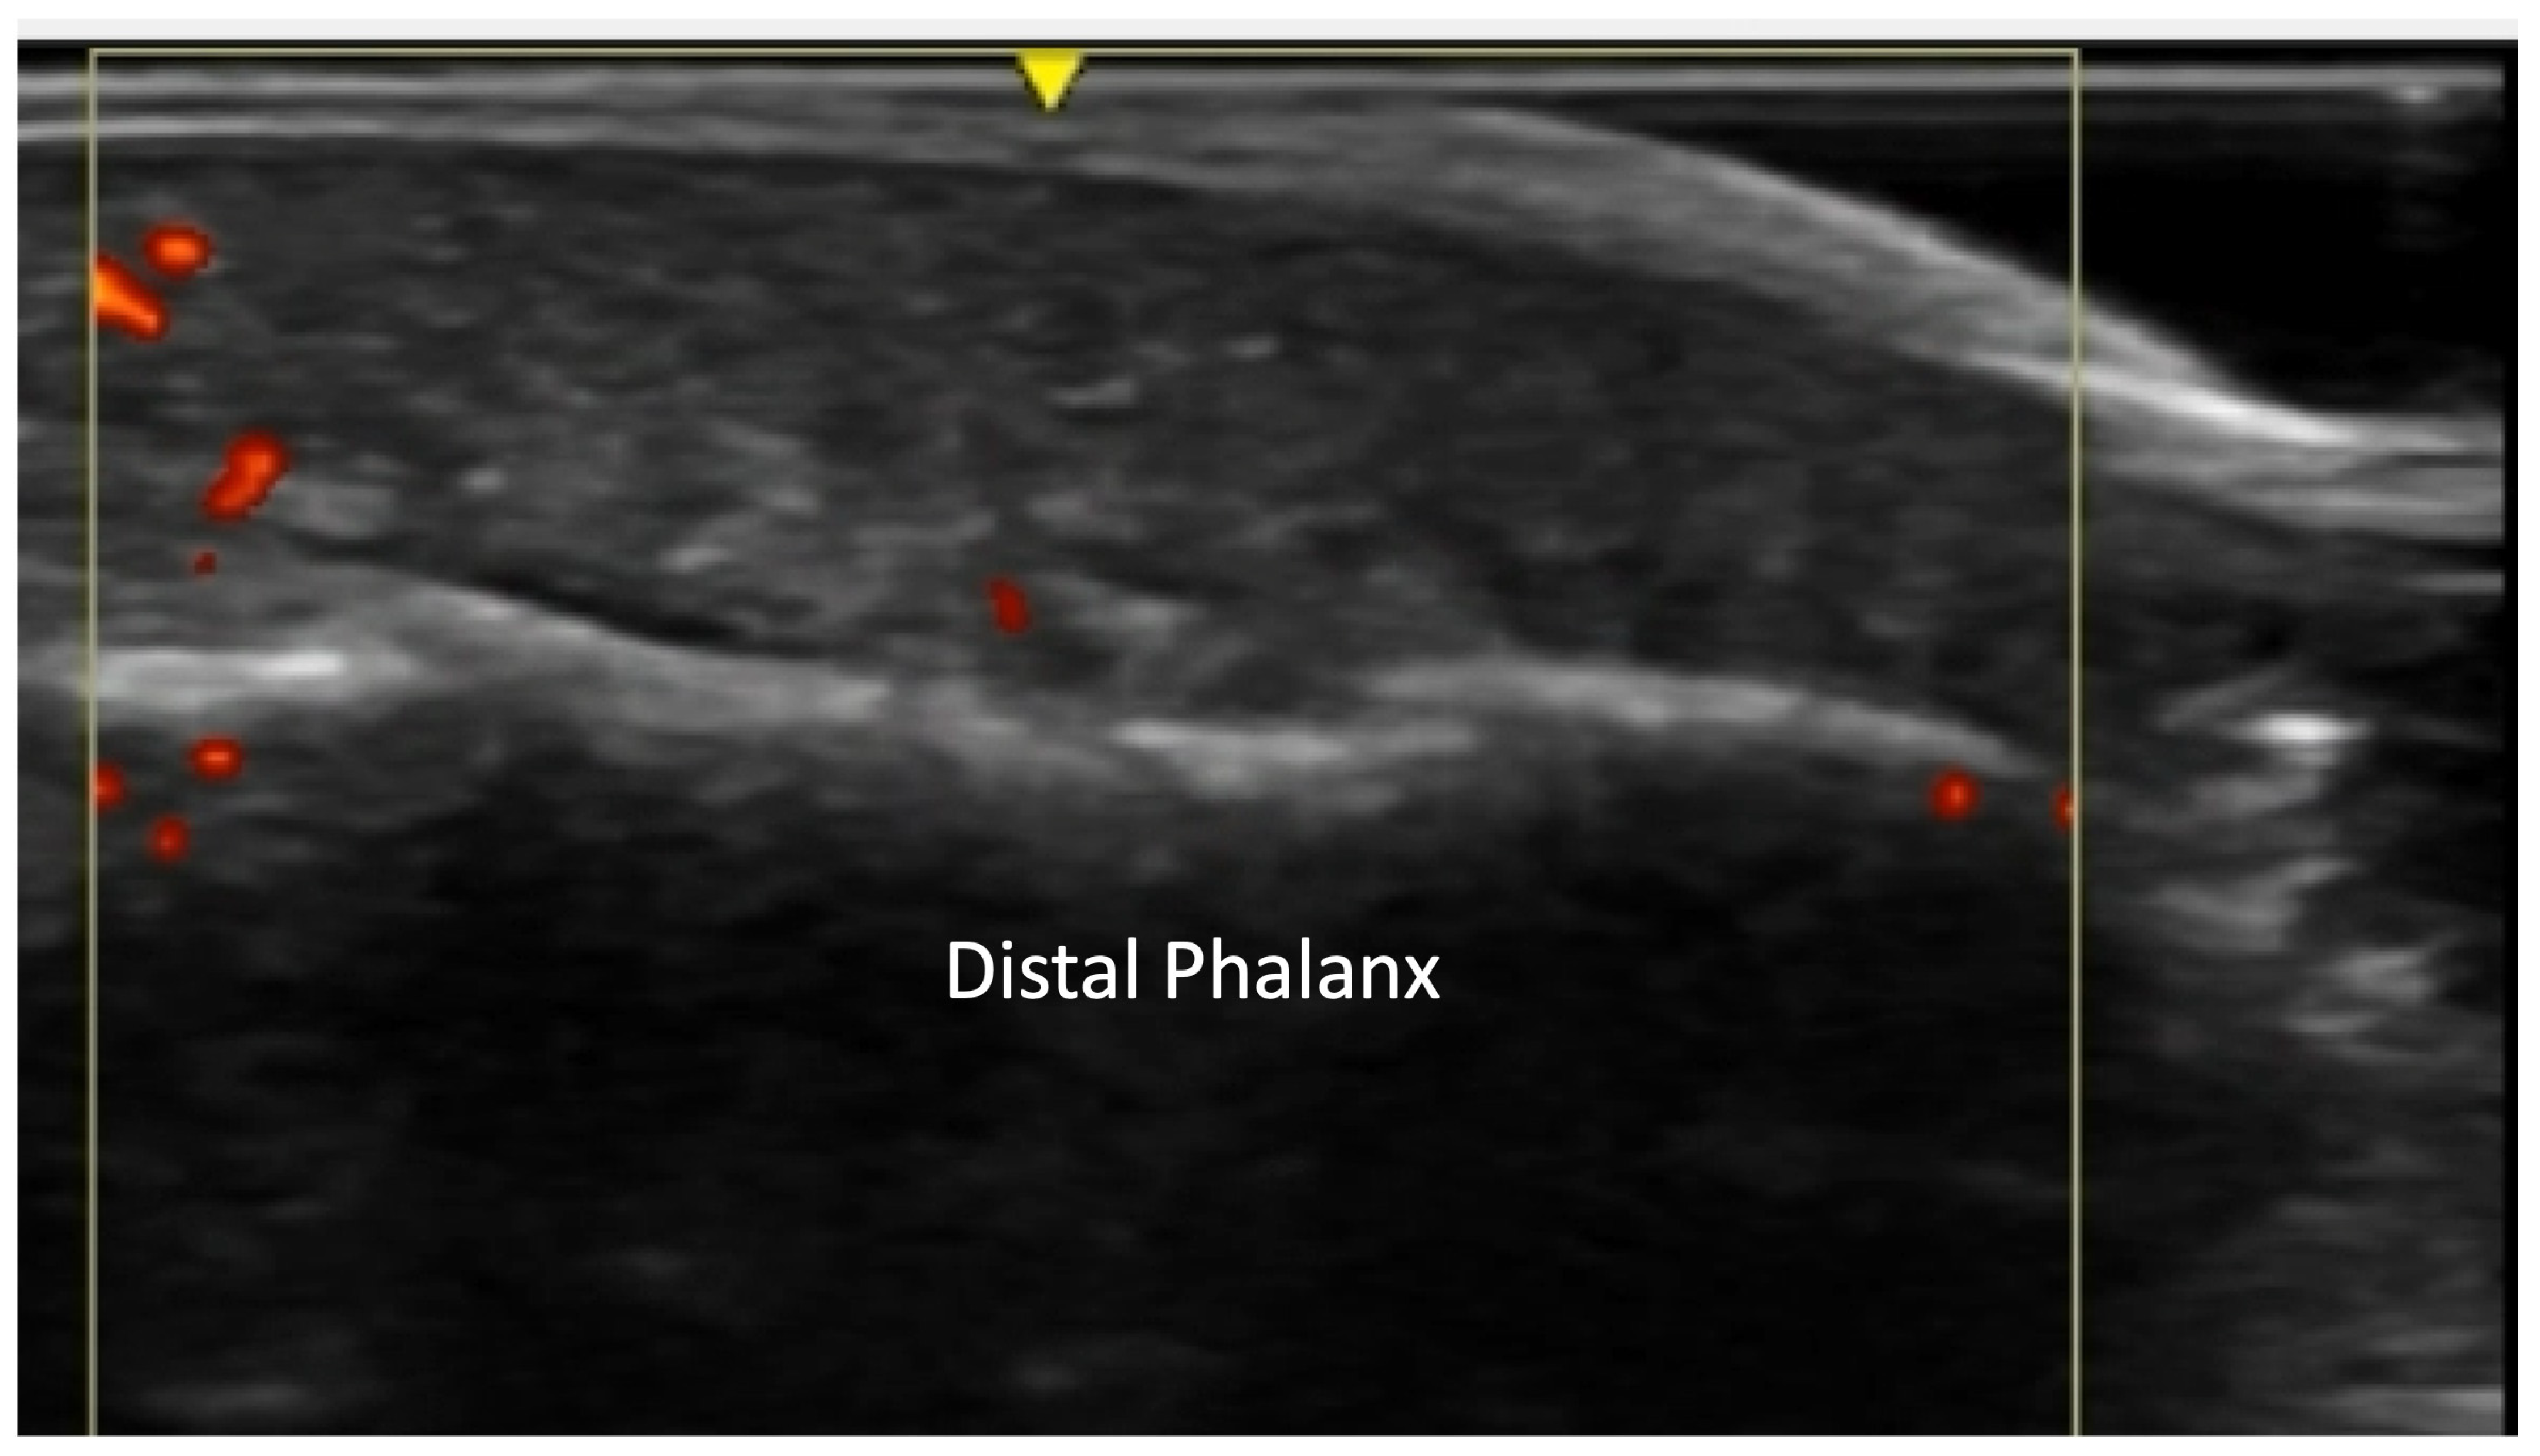

2.6. Calcium Deposition

4.2.3. Ulnar Aspect